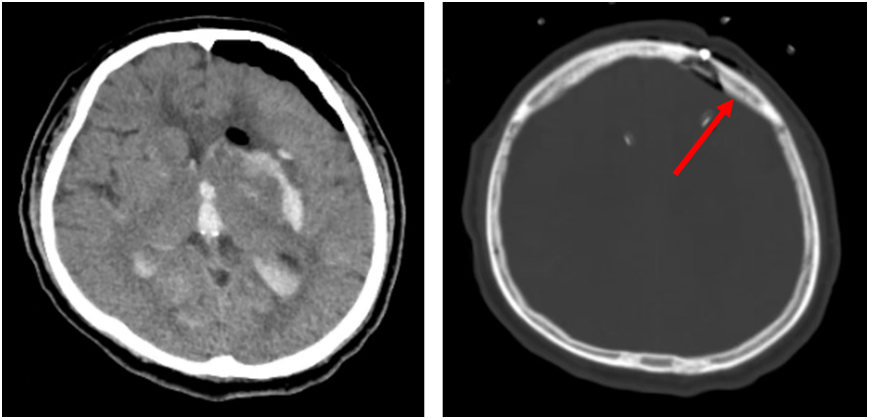

术后次日复查颅脑CT,右侧箭头所指为小骨窗。

术中,胡佳主任医师、薛昆副主任医师密切协作,以直切口的形式,开直径约3cm小骨窗,在神经内镜的直视下彻底清除脑内血肿。手术历时2个多小时结束。术后次日,患者神志转为清醒,复查显示,血肿清除理想。第2天,顺利拔除气管插管,返回神经外科病房。经过系统治疗后,患者恢复良好,并于术后第10天出院。